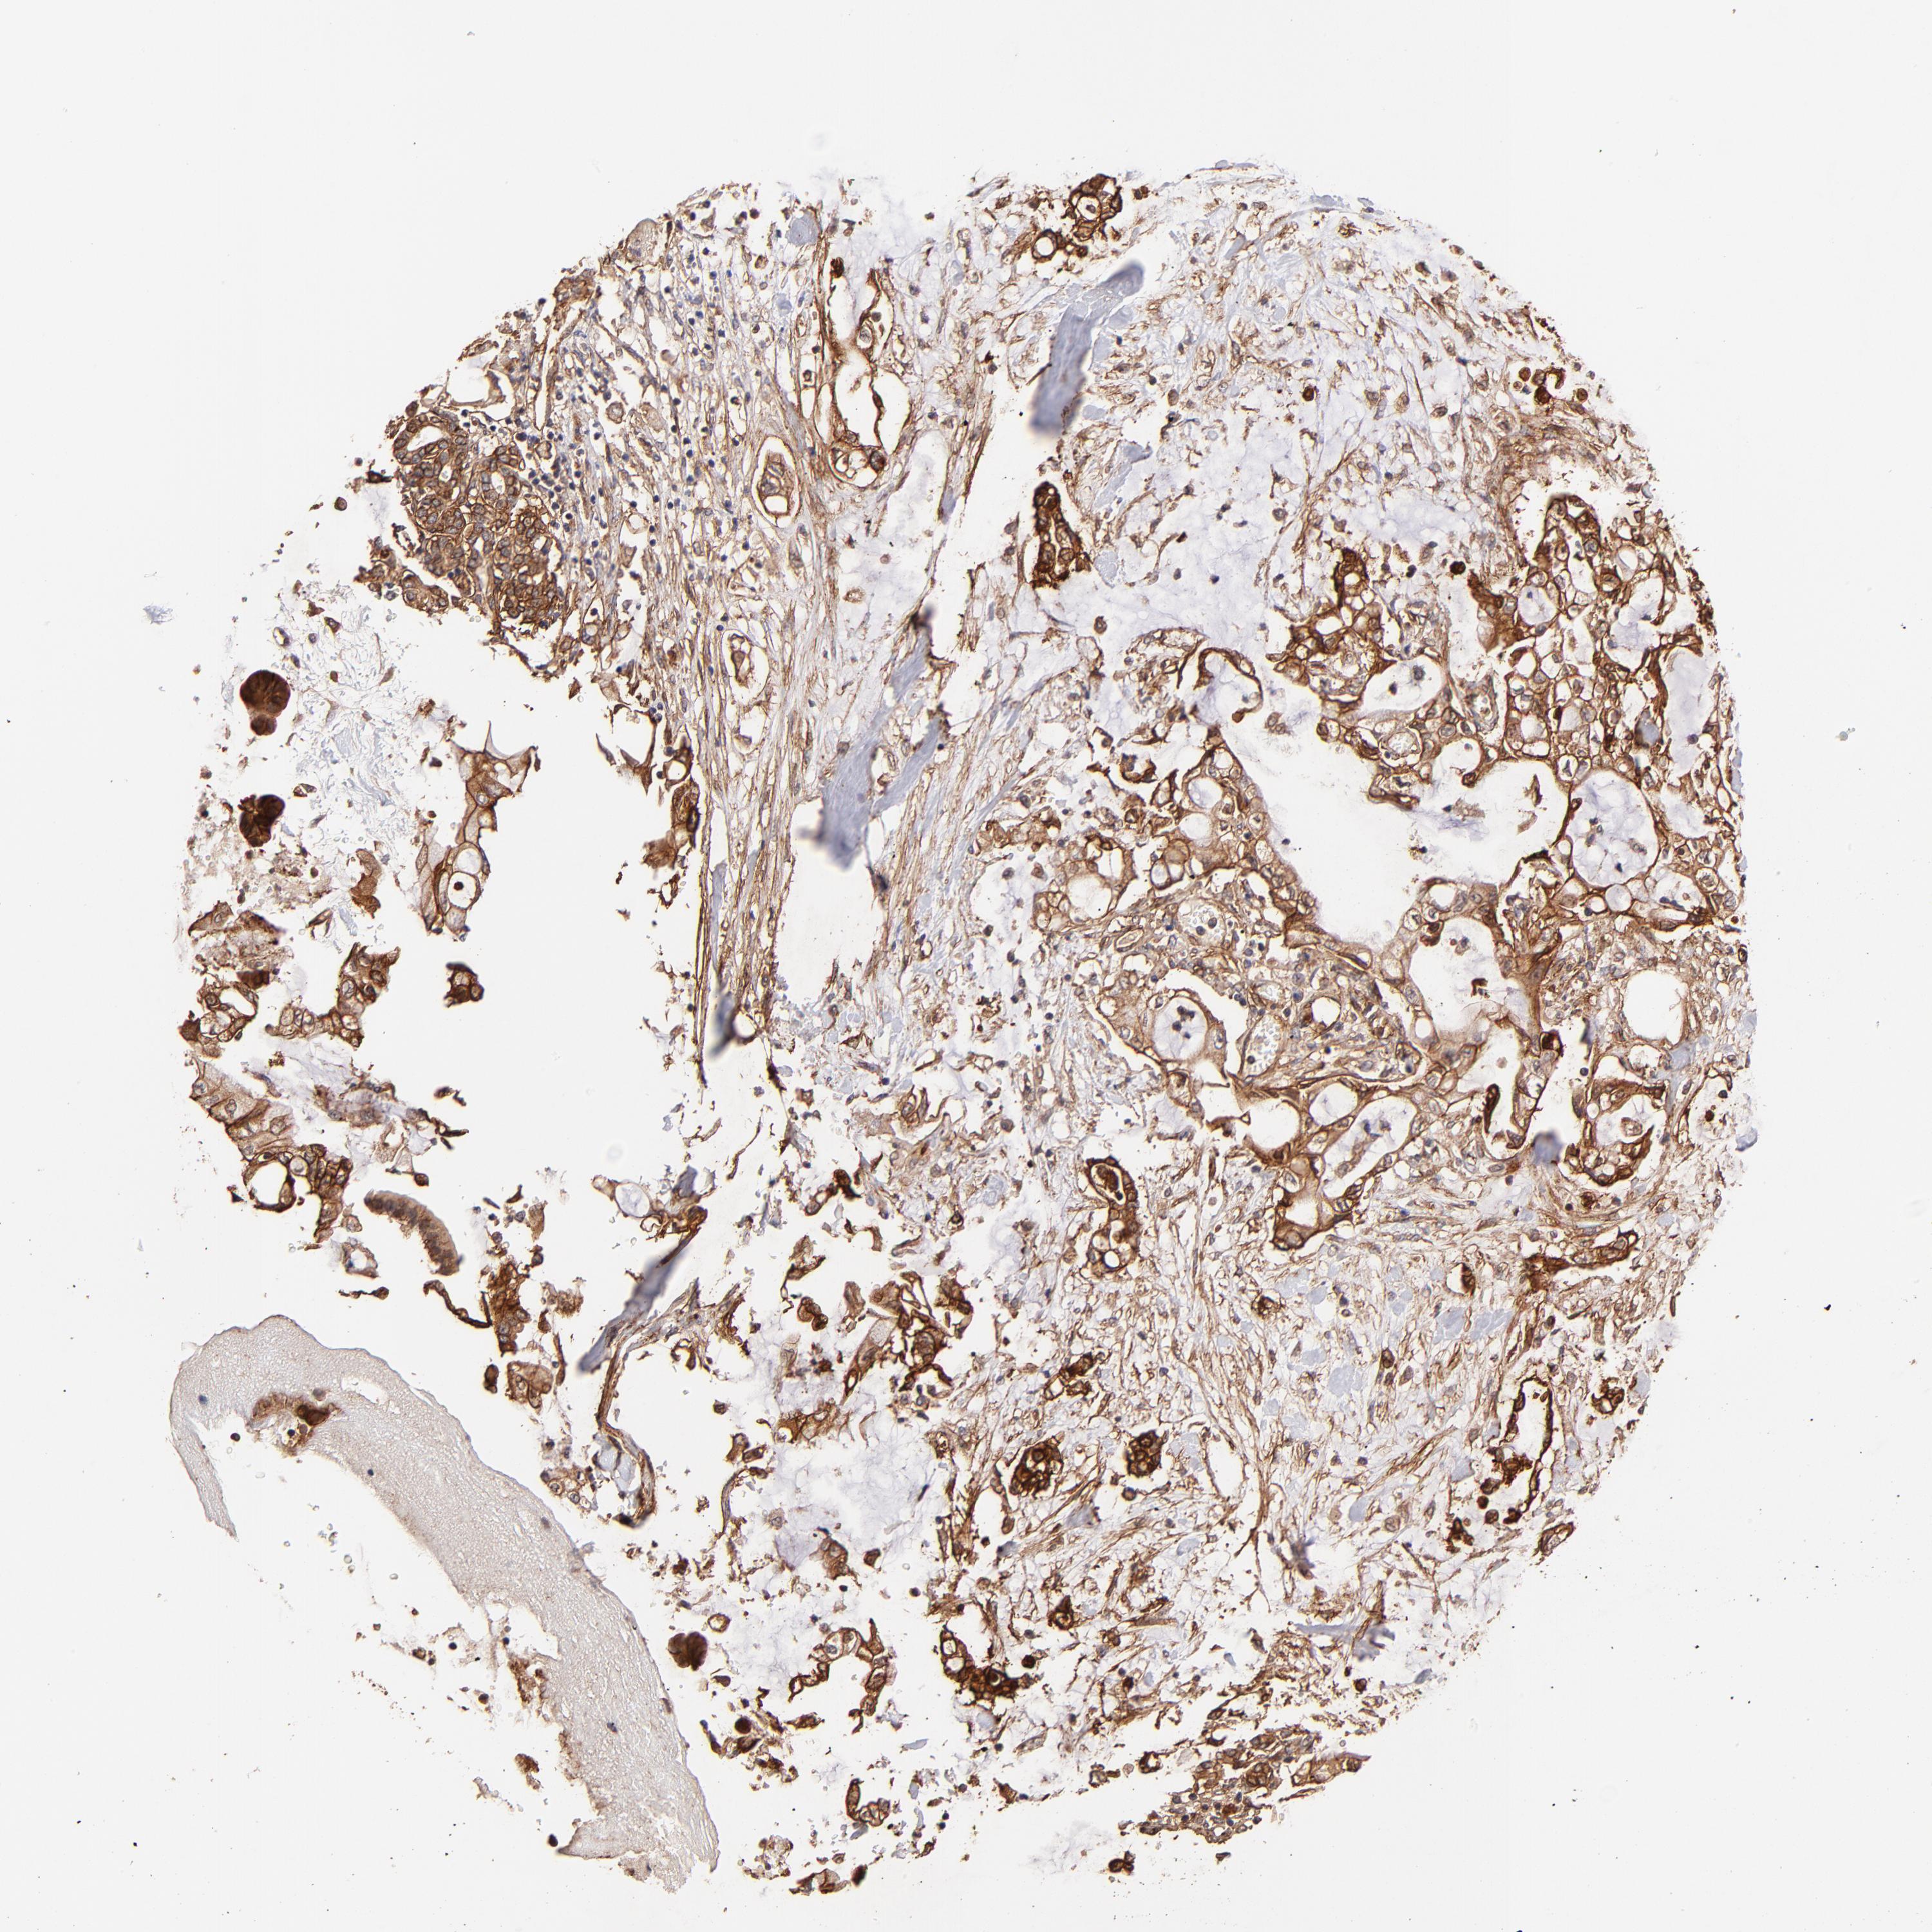

PANCREATIC CANCER - Protein expressioni

A mouse-over function shows sample information and annotation data. Click on an image to view it in a full screen mode. Samples can be filtered based on level of antibody staining by selecting one or several of the following categories: high, medium, low and not detected. The assay and annotation is described here.

Note that samples used for immunohistochemistry by the Human Protein Atlas do not correspond to samples in the TCGA dataset.

Antibody stainingi

Antibody staining in the annotated cell types in the current human tissue is reported as not detected, low, medium, or high, based on conventional immunohistochemistry profiling in selected tissues. This score is based on the combination of the staining intensity and fraction of stained cells.

Each image is clickable and will lead to virtual microscopy that enables deeper exploration of all samples and also displays staining intensity scores, fraction scores and subcellular localization as well as patient and tissue information for each sample.

Antibody HPA059297

Antibody HPA069003

Antibody CAB003434